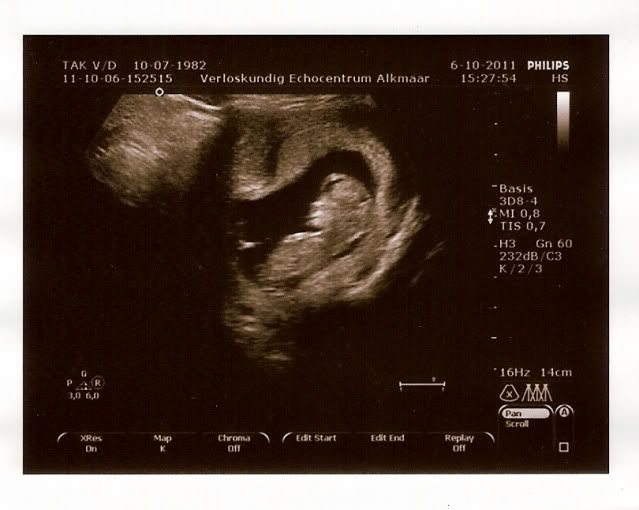

Dit is mijn gezichtje, mama vind dat ik nu al op papa lijk.